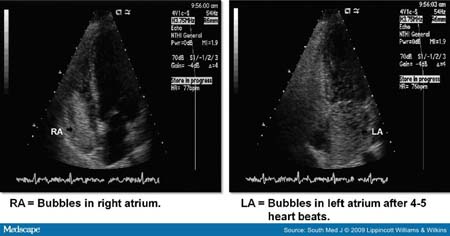

-Siêu âm đen trắng cho hình ảnh các tiểu bong bóng (> 10mm đường kính) do dung dịch muối bị lắc mạnh thường bị cản trở bởi mao mạch phổi (bình thường < 8 đến 15 mm) nhanh chóng di chuyển đến phổi và xuất hiện ở nhĩ trái của tim trong vòng 7 nhịp.